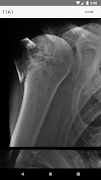

•高品質、拡大可能X線が含まれています